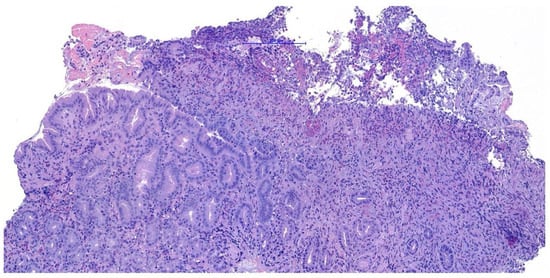

Histopathological examination of the gastric biopsies revealed mucosa with deep, hyperplastic crypts and occasional erosive and ulcerated areas replaced by necrotic and collagenous material containing abundant eosinophils, together with a mixed inflammatory infiltrate of neutrophils, small lymphocytes, and scattered eosinophils. Duodenal biopsies, including those obtained distal to the mass, showed irregular, shortened and fused villi with a moderate mixed lymphoplasmacytic infiltrate containing neutrophils and eosinophils in the lamina propria. Histopathological examination of the duodenal mass revealed a sample devoid of recognizable microanatomical architecture, composed of fibrocollagenous tissue interspersed with densely cellular areas (Figure 2). Overall, the findings were consistent with eosinophilic and fibroplastic gastroenteritis compatible with feline gastrointestinal eosinophilic sclerosing fibroplasia (FGESF).

Figure 2. Histological section of endoscopic duodenal biopsy showing dense eosinophilic infiltrates and marked fibroplasia with disrupted mucosal architecture H&E, 200×, scale bar = 200 µm.